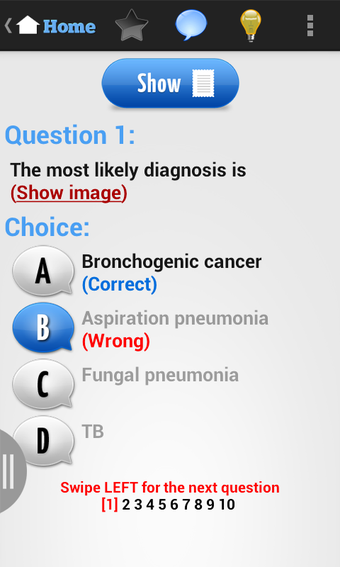

USMLE Exam Prep เป็นแอปพลิเคชัน Android ฟรีที่พัฒนาโดย quizworld ซึ่งเน้นการเตรียมความพร้อมอย่างละเอียดสำหรับการสอบ United States Medical Licensing Examination (USMLE) ให้แก่นักเรียน แอปพลิเคชันนี้ประกอบด้วยภาพพันธุกรรม ไฟล์เสียง และวิดีโอที่ครอบคลุมหลากหลายสาขา เช่น ชีวเคมีและพันธุกรรม รังสีหน้าอก วิธีการคลินิก อายุรศาสตร์ สูติศาสตร์และนรีวิทยา อายุรศาสตร์ประยุกต์ พยาธิวิทยา กุมารเวชศาสตร์ การวินิจฉัยทางกายภาพ ศัลยศาสตร์ จิตเวชศาสตร์ อาการสรีรวิทยา วิธีการคลินิก รังสีหน้าอก และการป้องกันโรค

นอกจากนี้ แอปพลิเคชันยังมีการ์ดฝึกหัดเพื่อช่วยให้นักเรียนปรับปรุงคำศัพท์และความรู้ในเชิงการแพทย์ แอปพลิเคชันนี้ใช้ง่ายและวัสดุการเรียนรู้จัดเรียงอย่างดี ทำให้นักเรียนสามารถนำไปใช้ได้อย่างง่ายดาย โดยรวมแล้ว แอปพลิเคชัน USMLE Exam Prep เป็นแหล่งข้อมูลที่ยอดเยี่ยมสำหรับนักเรียนที่กำลังเตรียมตัวสอบ USMLE และเป็นแนะนำอย่างมากสำหรับผู้ที่ต้องการเตรียมตัวสอบอย่างละเอียดและแบบปฏิสัมพันธ์